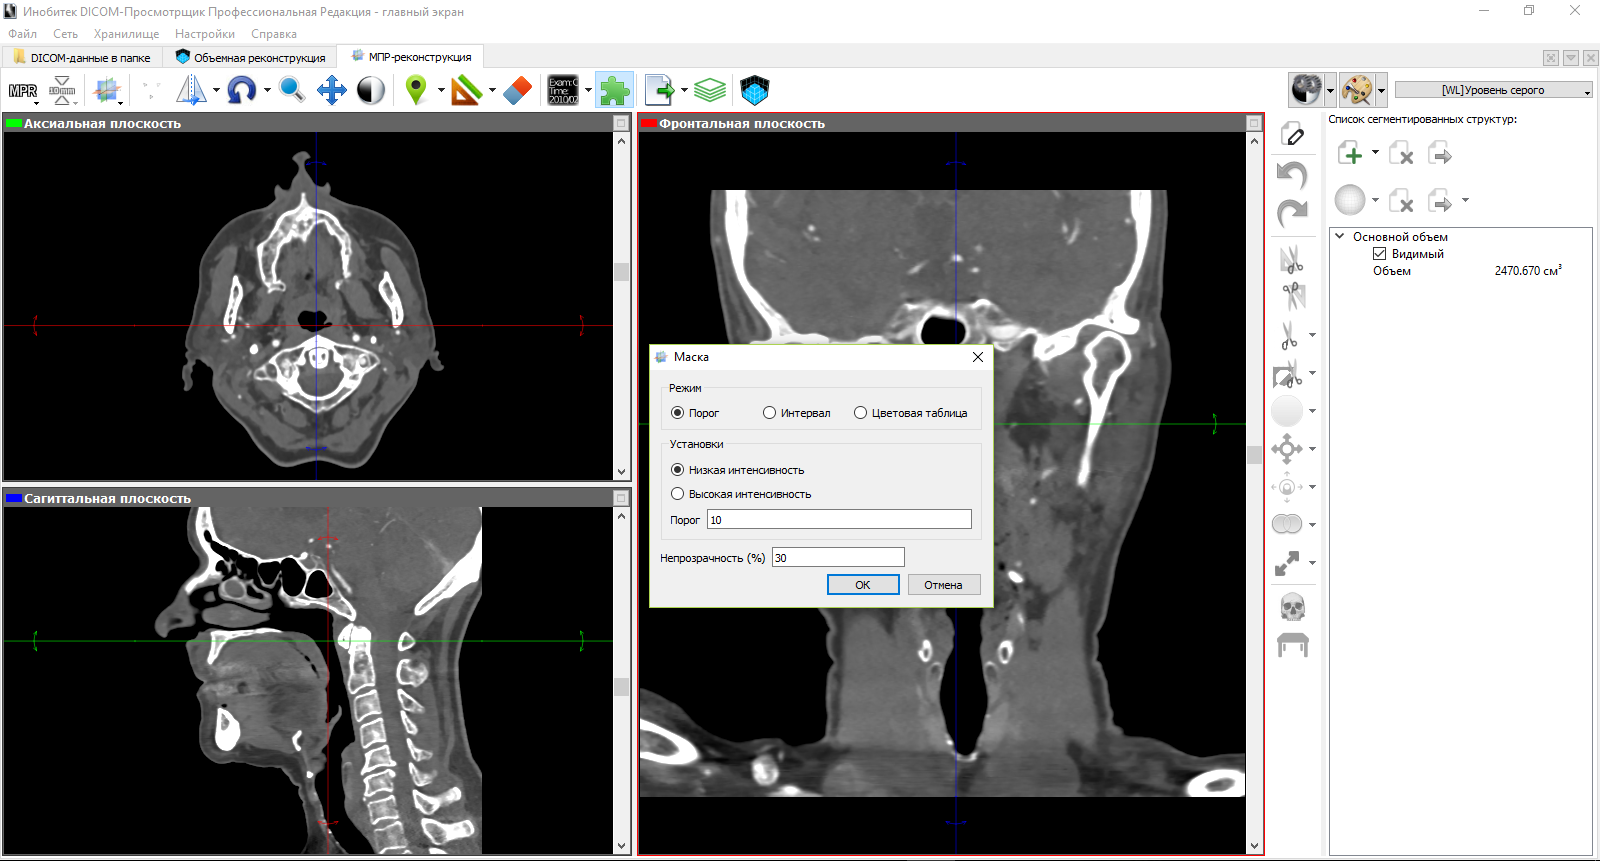

Лазерная камера сетевая для печати изображений на пленке стандарт dicom